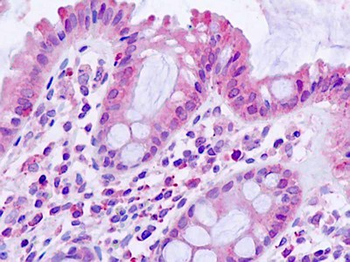

Anti-TGFBR1 / ALK5 antibody IHC staining of human small intestine. Immunohistochemistry of formalin-fixed, paraffin-embedded tissue after heat-induced antigen retrieval.